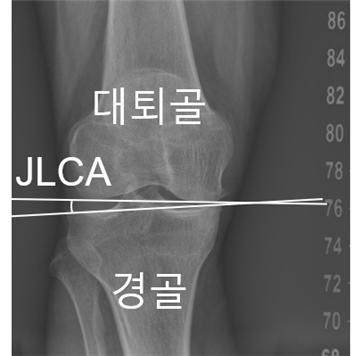

연구 결과, 무릎 관절을 이루는 뼈 사이 간격을 나타내는 '관절선 수렴각(JLCA)'이 정렬 변형을 가속화하는 주요 지표로 밝혀졌다.

무릎 관절 정렬의 변화 양상과 변형 속도를 좌우하는 핵심 요인이 확인됐다. 연구 결과, 무릎 관절을 이루는 뼈 사이 간격을 나타내는 ‘관절선 수렴각(JLCA)’이 정렬 변형을 가속화하는 주요 지표로 밝혀졌다.

연구팀은 인공지능(AI) 기반 소프트웨어를 활용해 하지 엑스레이를 분석하고, 엉덩이-무릎-발목 각도(HKAA), 관절선 수렴각(JLCA), 관절염 중증도(K-L 등급) 등 주요 지표를 측정했다. 이후 HKAA를 기준으로 하지를 O자형, 중립, X자형으로 구분하고, 정렬 변화가 연간 0.5도 이상인 경우를 ‘가속 진행’으로 정의해 분석을 진행했다.

연구팀은 관절선 수렴각(JLCA)이 이러한 가속 진행을 예측하는 공통 지표임을 밝혀냈다. 초기 JLCA가 1도 증가할 때마다 O자형 환자에서는 가속 진행 위험이 12.9%, X자형 환자에서는 19.4%씩 높아지는 것으로 나타났다.